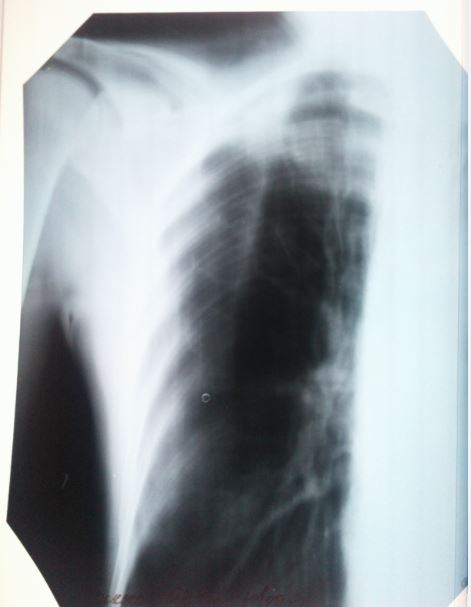

Здравствуйте,еще раз. Как сказала врач, в направлении там где написано " диагноз " - это то что показывают снимки.

Как еще врач говорит. По анализам все хорошо , по диаскинтест - отрицательно. Видимых симптомов нет , при осмотре-прослушивании тоже все хорошо. Как тогда может быть такой диагноз? Нет ни температуры.ни отдышки,ни головной боли,вес не теряла,не худела резко,в семье ни у кого такого не было.на учете не состояла. просто как так может быть что по снимкам развие " болезни " есть , а по анализам и тесту нет ?

Здравствуйте. Да, действительно случаи бывают разные. Тем и коварен уберкулез, что распознать его удается не всегда, и симптомов явным может не быть, и анализы могут не показывать всей картины. Но диагноз врач выставил на законных основаниях - изменения в легких типичны для туберкулеза. Консультируйтесь в областном центре, можно также сделать КТ (компьютерную томографию), ведь этот метод более точен, чем рентген.